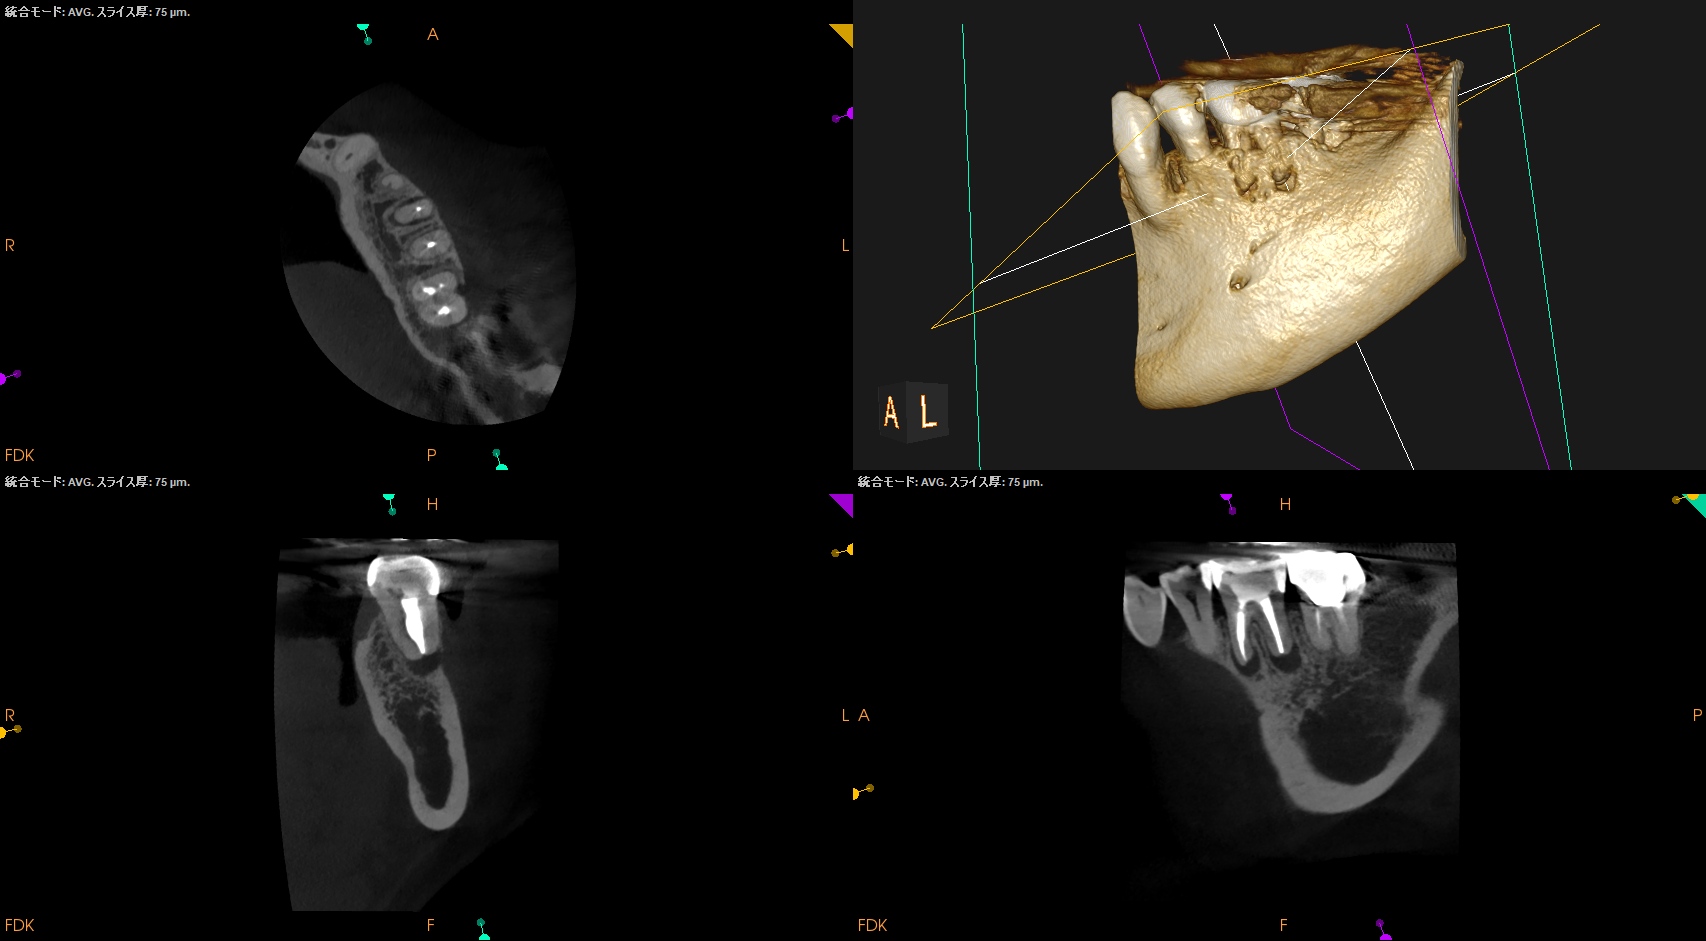

CBCT(2025.9.16)

MB

ML

D

MにもDにも病変がある。

B

頬側の骨がない。

これが圧痛に対する反応の原因だ。